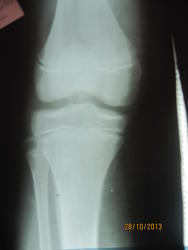

Кстати а 2и 3 снимок, где лево и право?

Подписала

Такое ощущение, что бугристость болшеберцовой кости фрагментирована справа.

Не похоже, чтобы тянул левый коленный сустав на артрит.

А на Осгуд-Шлаттера не тянет слева?